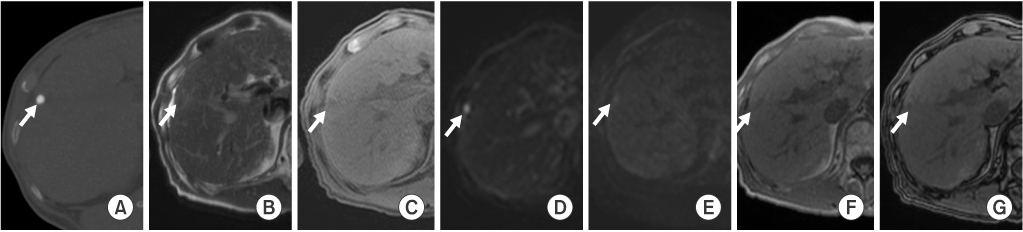

Among the 16 dense LHCCs in group A, eight LHCCs (53%) showed high SI, and five LHCCs (33%) showed iso SI on T2WI. Ten LHCCs (63%) showed low SI, and three LHCCs (19%) showed iso SI on T1WI. At b values of 0, 50 400, and 800, high SI was seen on DWI in seven, eight, eight, and five LHCCs, respectively. Six LHCCs (38%) showed decreased SI when compared to liver parenchyma at higher DWI b values of 400 and 800. Nine LHCCs (56%) showed high SI on in-phase gradient-echo images (GE), and ten LHCCs (63%) showed low SI on out-of-phase GE. None of the 16 LHCCs were enhanced on dynamic contrast-enhanced images (Table 1, Fig. 2).

Fig. 2

MR images of a 69-year-old patient with a 1.9×1.3 cm-sized dense hepatocellular carcinoma with lipiodol uptake in hepatic segment 5. Hepatocellular carcinoma (arrows) shows dense uptake of lipiodol on precontrast computed tomography with bone window setting (A), high signal intensity on T2-weighted images (B), and low signal intensity on T1-weighted images (C). On diffusion-weighted images, it reveals high signal intensity at lower b factors (b=0 and b=50) (D and E, respectively) and decreased signal intensity at a higher b factor (b=800) (F). The lesion shows high signal intensity on in-phase gradient-echo images (G) and low signal intensity on out-of-phase gradient-echo images (H). It is not enhanced on dynamic contrast-enhanced arterial phase (I), portal phase (J) or 10-minute delayed phase (K) images.

Fig. 2 MR images of a 69-year-old patient with a 1.9×1.3 cm-sized dense hepatocellular carcinoma with lipiodol uptake in hepatic segment 5. Hepatocellular carcinoma (arrows) shows dense uptake of lipiodol on precontrast computed tomography with bone window setting (A), high signal intensity on T2-weighted images (B), and low signal intensity on T1-weighted images (C). On diffusion-weighted images, it reveals high signal intensity at lower b factors (b=0 and b=50) (D and E, respectively) and decreased signal intensity at a higher b factor (b=800) (F). The lesion shows high signal intensity on in-phase gradient-echo images (G) and low signal intensity on out-of-phase gradient-echo images (H). It is not enhanced on dynamic contrast-enhanced arterial phase (I), portal phase (J) or 10-minute delayed phase (K) images.